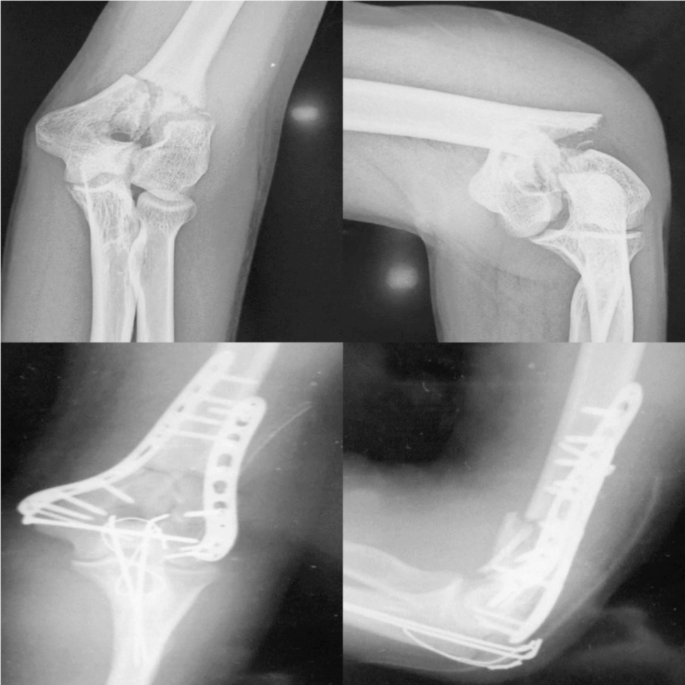

Group B: Internal fixation via the orthogonal plating method (21 patients). (Fig. 3)

A 31-year-old male patient with a distal humerus fracture.

The patient underwent an operation via the orthogonal plating method.

a.

Anteroposterior and lateral initial plain radiographs.

-

b.

Anteroposterior and lateral postoperative plain radiographs at 2 weeks.

postoperatively.